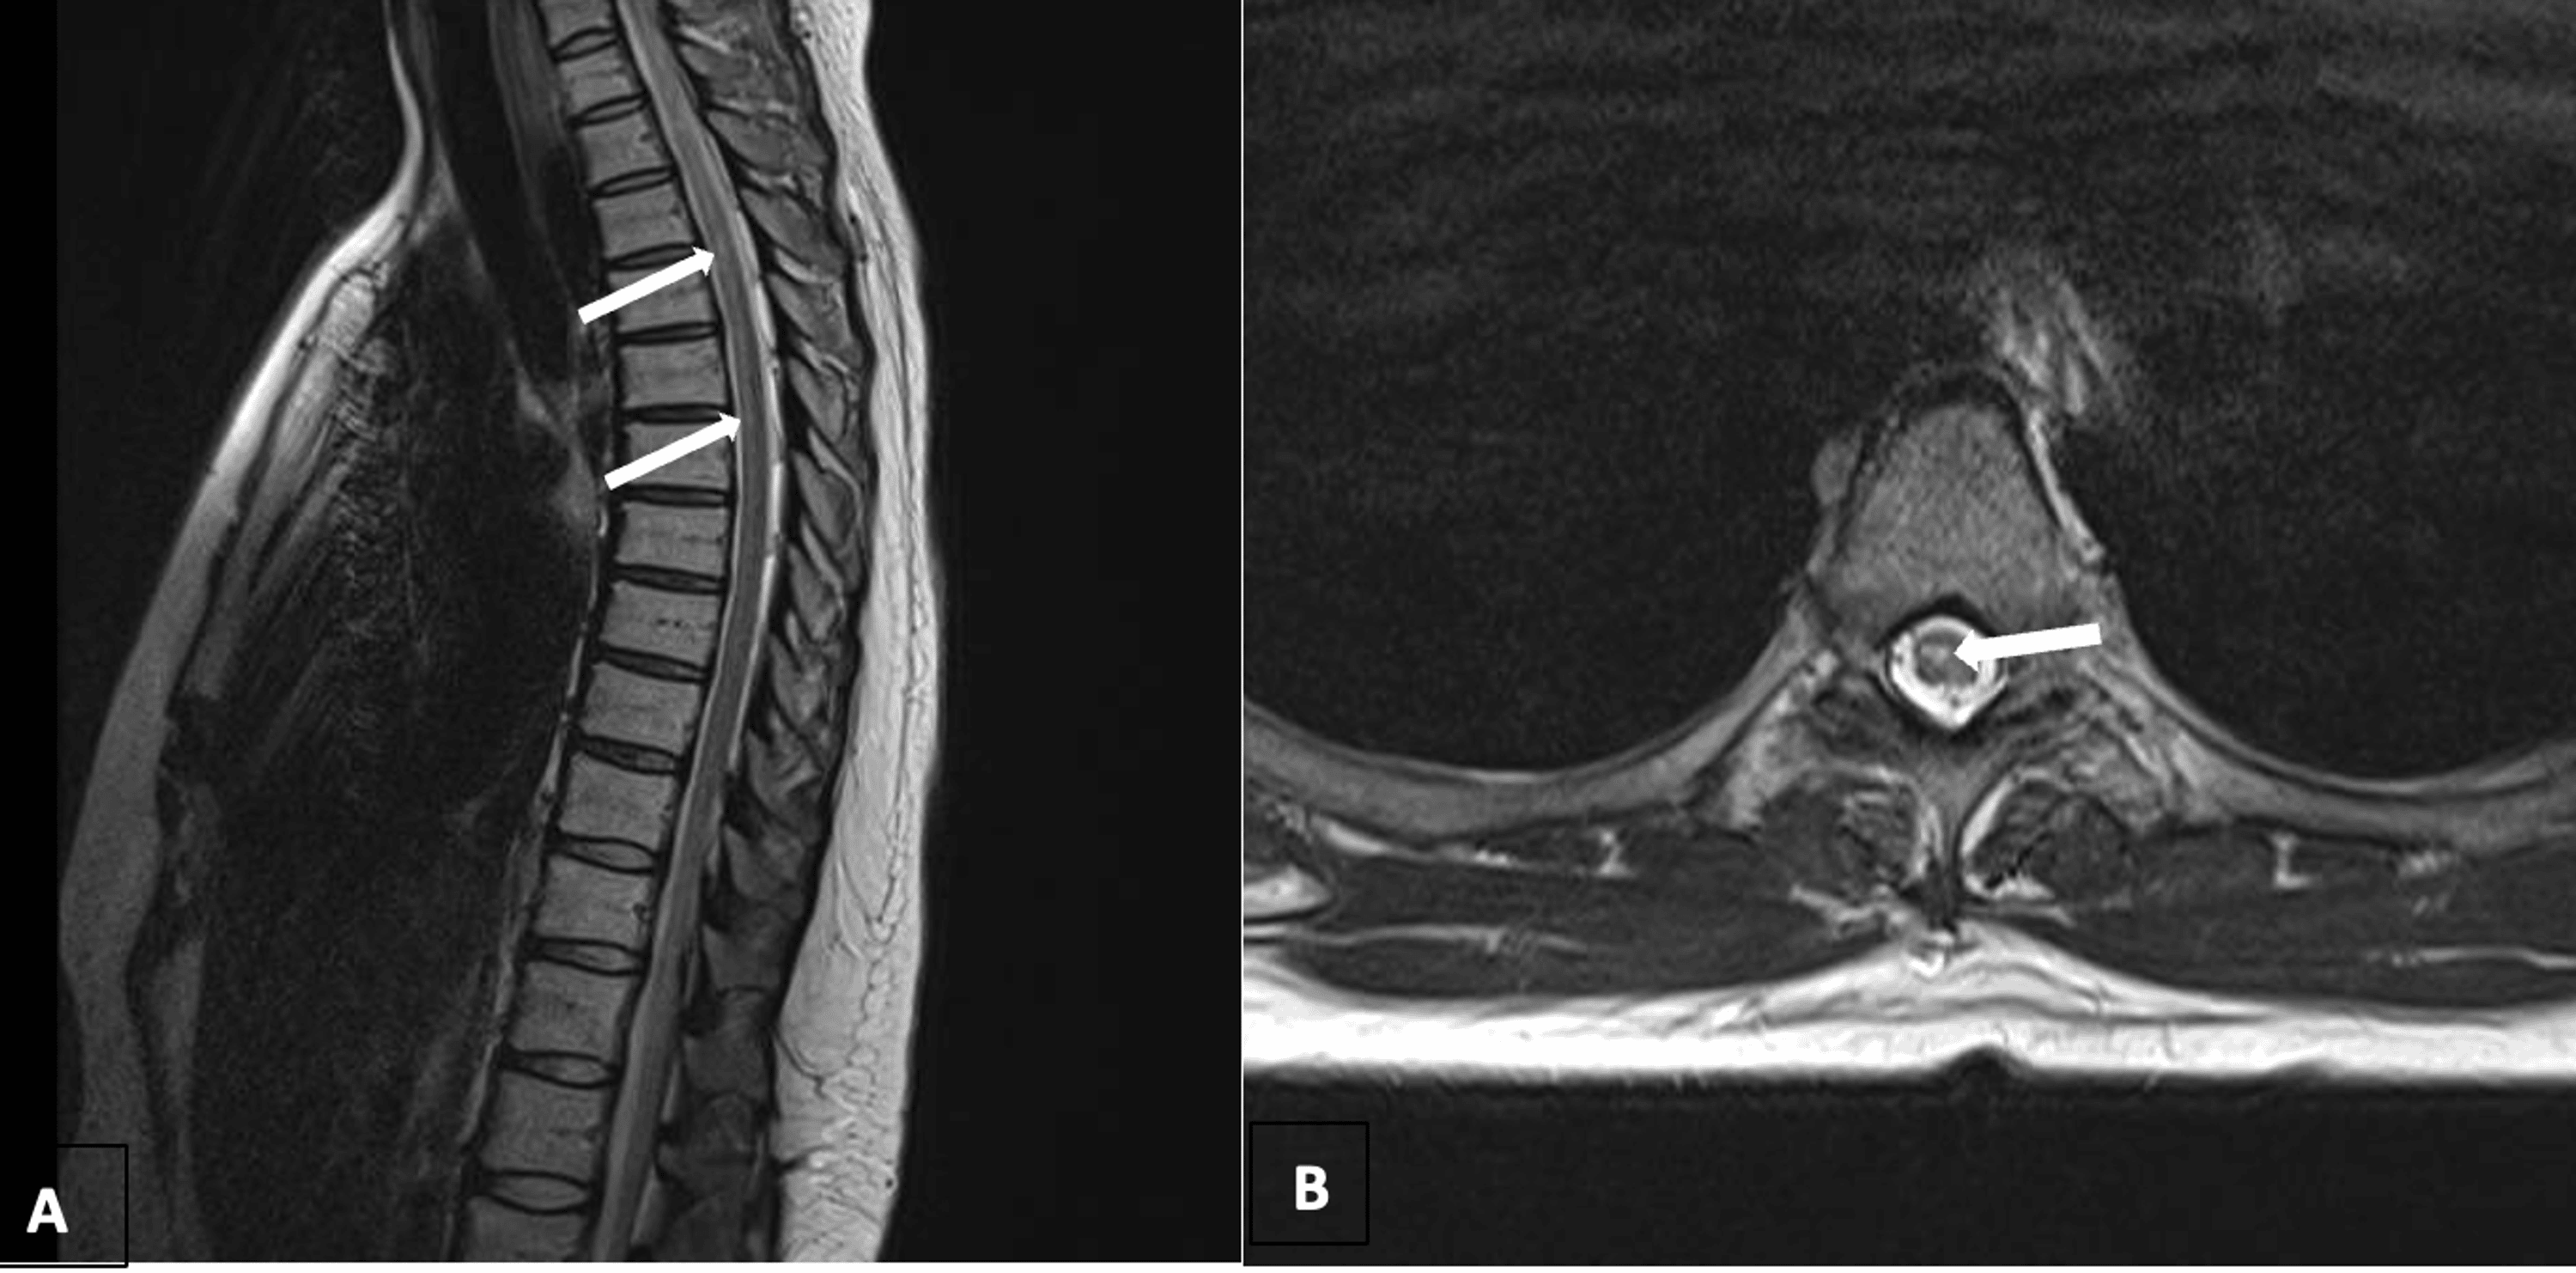

Figure 1 from Dynamic Compression of the Spinal Cord by Paraspinal Flexion Extension Mri Near Me The cervical spine flexion and extension views demonstrate the seven vertebrae of the cervical spine when the patient is in a. The purpose of the study was to determine the value and utility of flexion and extension mr imaging in traumatized cervical. This type of diagnostic imaging. Flexion and extension mri allows the physician to see the patient’s neck not. Flexion Extension Mri Near Me.